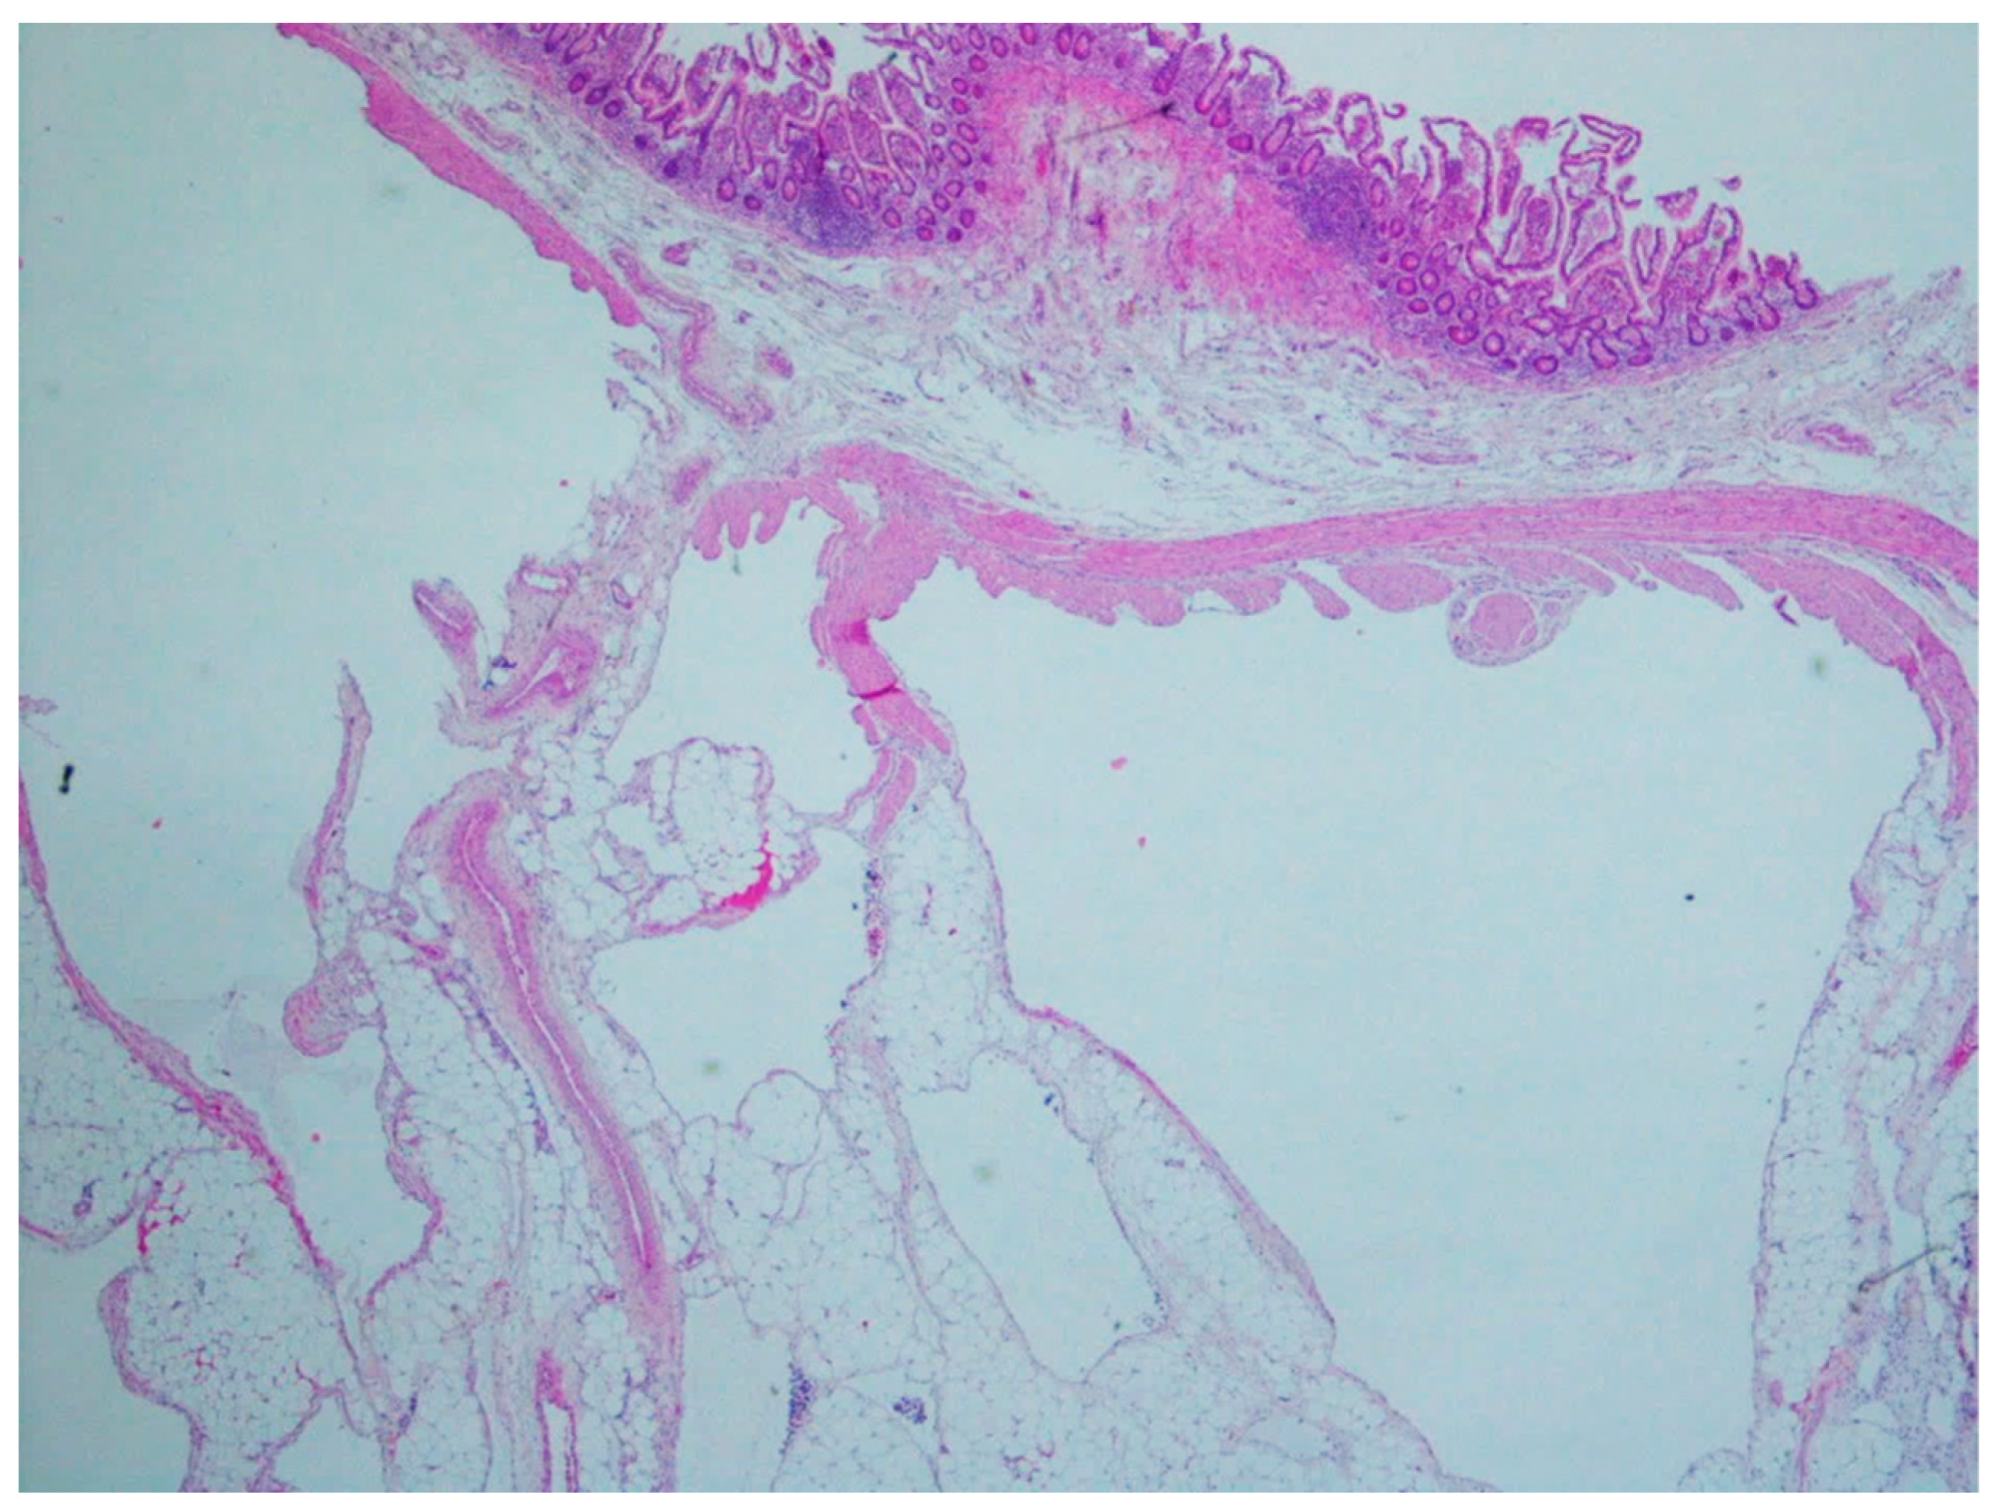

| Lymphangiomas | Children and young adults | Small intestine | Anemia or acute abdomen | Thin-walled, cystically dilated lymphatic spaces lined by endothelial cells with lymph fluid | D2-40, CD31, CD34 |